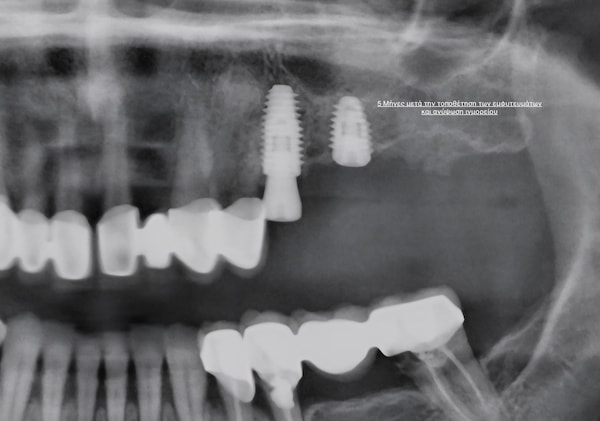

Κατά τη διάρκεια των επόμενων περίπου 4 μηνών, το εμφύτευμα ενσωματώνεται στο οστό (οστεοενσωμάτωση), δημιουργώντας μια σταθερή και φυσική δομή που αντικαθιστά τη ρίζα του δοντιού.

Μετά την πλήρη ενσωμάτωση, τα εμφυτεύματα “αποκαλύπτονται” και τοποθετείται ένας κοχλίας επούλωσης, που βοηθά στη διαμόρφωση των ούλων γύρω από τη μελλοντική στεφάνη.

Μετά από 2–3 εβδομάδες, λαμβάνεται αποτύπωμα και το δείγμα αποστέλλεται στο οδοντοτεχνικό εργαστήριο, όπου κατασκευάζεται η τελική αποκατάσταση.

Η συνολική διαδικασία, από την πρώτη επίσκεψη μέχρι την τελική τοποθέτηση του δοντιού, διαρκεί περίπου 4–5 μήνες.